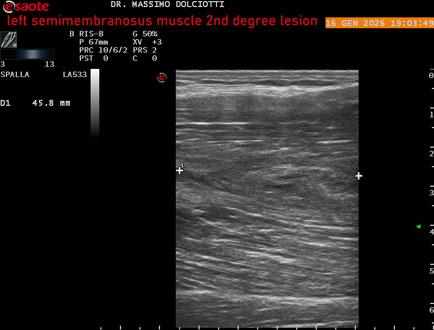

Data inserimento: 23/01/2026

Ecografia del: 16/01/2025

Strumento: Esaote MyLab Eight

Sonda: Lineare Multifrequenza 3-13 MHz

Età Paziente: M 23 anni

Motivazione dell'esame: dolore coscia sinistra da tre giornii.

Commento all'esame: le immagini ed il video documentano il muscolo semimembranoso sinistro disomogeneo per area iso-ipoecogena delle dimensioni di 38 x 14,7 mm per asse corto trasversale, 81 x 22 mm per asse longitudinale, come da lesione di 2° grado, con minimo versamento siero-ematico intramuscolare.

Conclusioni: lesione di 2° grado del muscolo semimembranoso sinistro (2nd degree lesion of the left semimembranosus muscle).